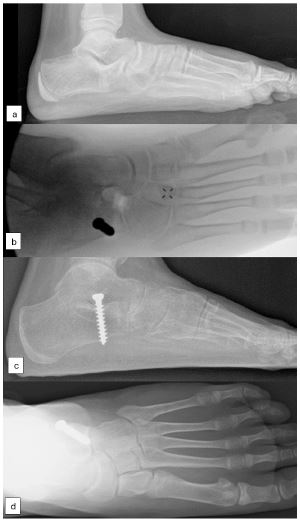

Figure 1: Preoperative standing radiograph of calcaneo-navicular coalition (A); Intraoperative fluorogram (B); Corrected calcaneal pitch, talo-navicular coverage and Meary’s angle after coalition excision and arthroereisis (C,D).

The author’s preferred method of arthroereisis involves the insertion of a 6.5 mm cancellous bone screw (AO large fragment set) near the anterolateral edge of the posterior facet of the subtalar joint, positioned under the lateral process of the talus. This screw functions as a calcaneo-stop screw, preventing excessive hindfoot eversion and maintaining the subtalar joint in a more aligned position (Figure 1). At the end of procedure, the foot alignment evaluated to exclude hindfoot valgus overcorrection. The decision of gastrocnemius recession was made at the end of the procedure based on Silfverskiöld test.